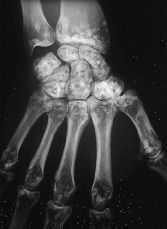

Para descartar una enfermedadsistematizada (por ejemplo, metástasis osteocondensantes) serealiza un estudio radiológico esquelético donde seencuentran imágenes similares de moteado irregular a nivelde muñecas y manos (fig. 2), pies (fig. 3), y rodillas (fig.4).

Figura2.